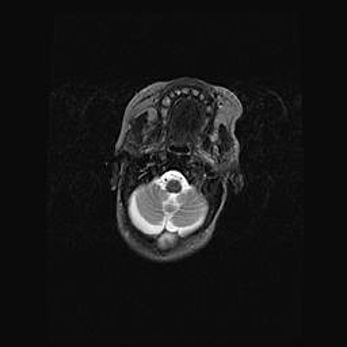

Мальформация Денди-Уокера. Киста задней черепной ямки.

Агенезия мозолистого тела.

Возраст: 2,5 месяца

Вес: 2420 г

Пол: женский

Окружность головы: 37 см

Срок гестации: 32 недели

Мальформация Денди—Уокера — редкий вид патологии ЦНС, представляющий собой врожденный порок развития каудального отдела ствола и червя мозжечка, ведущий к неполному раскрытию срединной (Мажанди) и латеральных (Лушка) апертур IV желудочка мозга. Для этогно синдрома характерна триада симптомов: гипотрофия червя мозжечка и/или полушарий мозжечка, кисты задней черепной ямки, гидроцефалия различной степени. В 70% случаев порок сочетается и с другими аномалиями головного мозга, в частности с агенезией мозолистого тела.